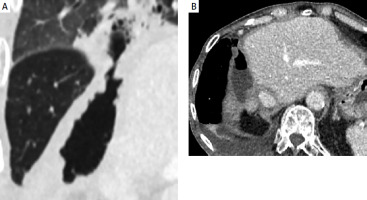

Figure 4

A – Contrast-enhanced CT coronal plane showing hepatopleural fistula. B – Contrast-enhanced CT axial plane showing hepatopleural fistula with fluid and gas

One month after surgery, the patient again presented with fever and chills. Imaging studies demonstrated a hepatopleural fistula (Figure 4). Due to the patient’s refusal of surgery, percutaneous drainage was performed. Repeated exchanges of the drainage were required over the following 3 years (Figure 5). The patient remained free of disease progression but ultimately died due to cardiovascular causes 3.4 years after RL.